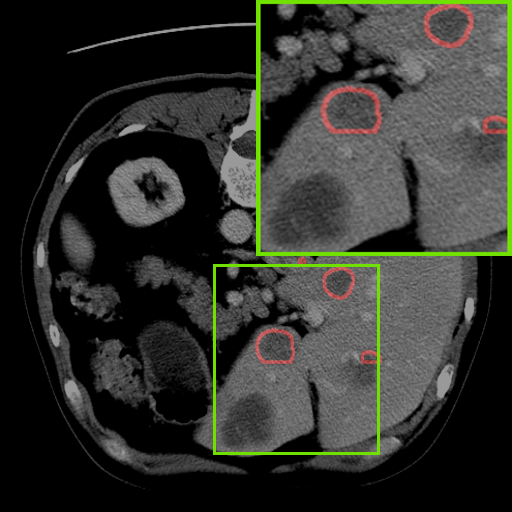

Figure 3: Qualitative comparison visualization of DEAP-3DSAM and baselines on four datasets.

IV-B2 Qualitative Performance Comparison

We also performed qualitative analysis on four datasets. As illustrated in Fig. 3, DEAP-3DSAM accurately identifies the target regions and closely matches their size. In contrast, 3DSAM-Adapter [3dsamadapter] exhibits limitations in matching the size and shape of the target regions. This proves that DEAP-3DSAM captures more complex image features, owing to its Dual Attention Prompter and Feature Enhanced Decoder. Furthermore, while these SAM-based methods are nearly capable of localizing the target regions, many traditional methods, i.e. UNETR++ [unetr++], Swin-UNETR [swinunetr], and TransBTS [transbts], struggle to achieve this. This highlights the potential of SAM-based methods for addressing complex 3D segmentation tasks.